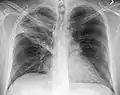

Normal AP CXR

Normal lateral CXR

AP CXR showing left lower lobe pneumonia associated with a small left sided pleural effusion

AP CXR showing right lower lobe pneumonia

AP CXR showing pneumonia of the lingula of the left lung

Right upper lobe pneumonia as marked by the circle.

Left upper lobe pneumonia with a small pleural effusion.

Right lower lobe pneumonia as seen on a lateral CXR